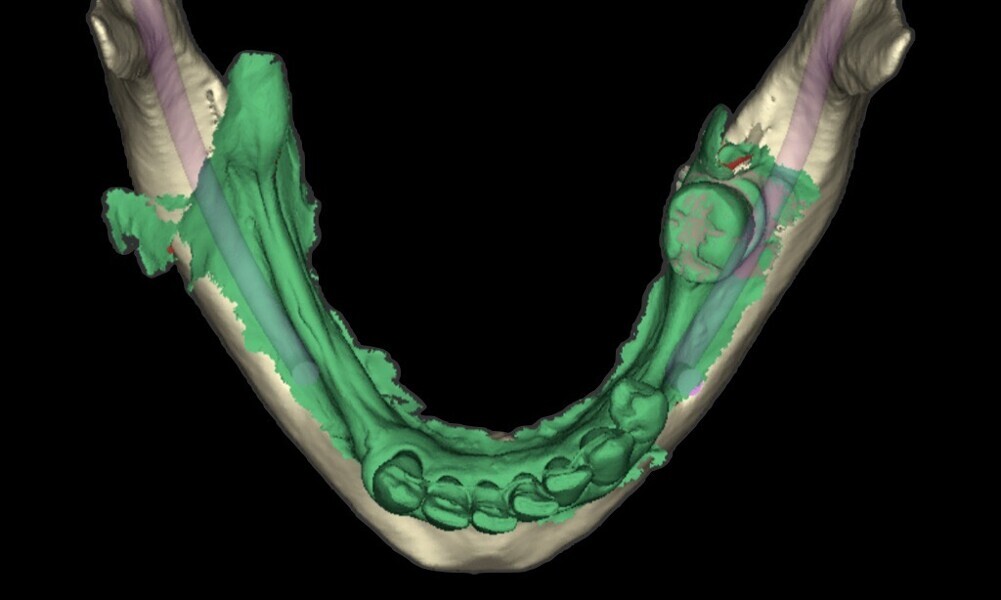

To ensure precise and predictable treatment planning, the DICOM files, STL files and clinical photographs were seamlessly integrated into Smilecloud, utilising advanced artificial intelligence technologies to deliver a highly personalised smile with exceptional precision (Figs. 11–15).

Figs. 11–15: DICOM files, STL files and clinical photographs were integrated into Smilecloud, leveraging artificial intelligence for precise, personalised smile design.